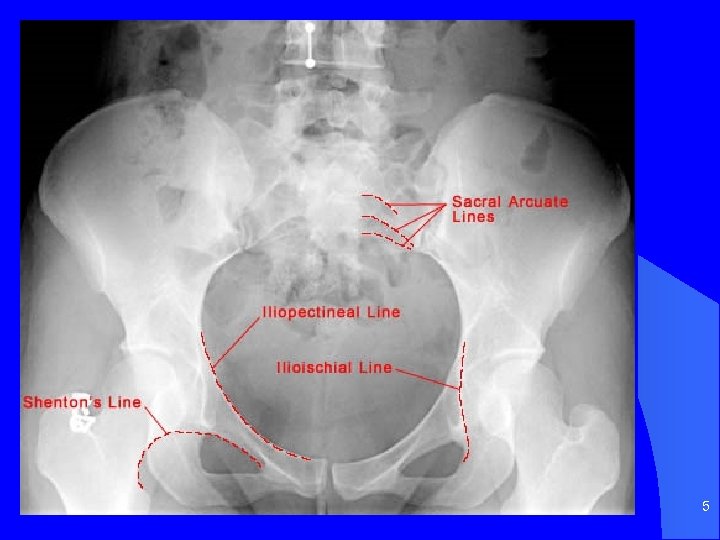

4

5